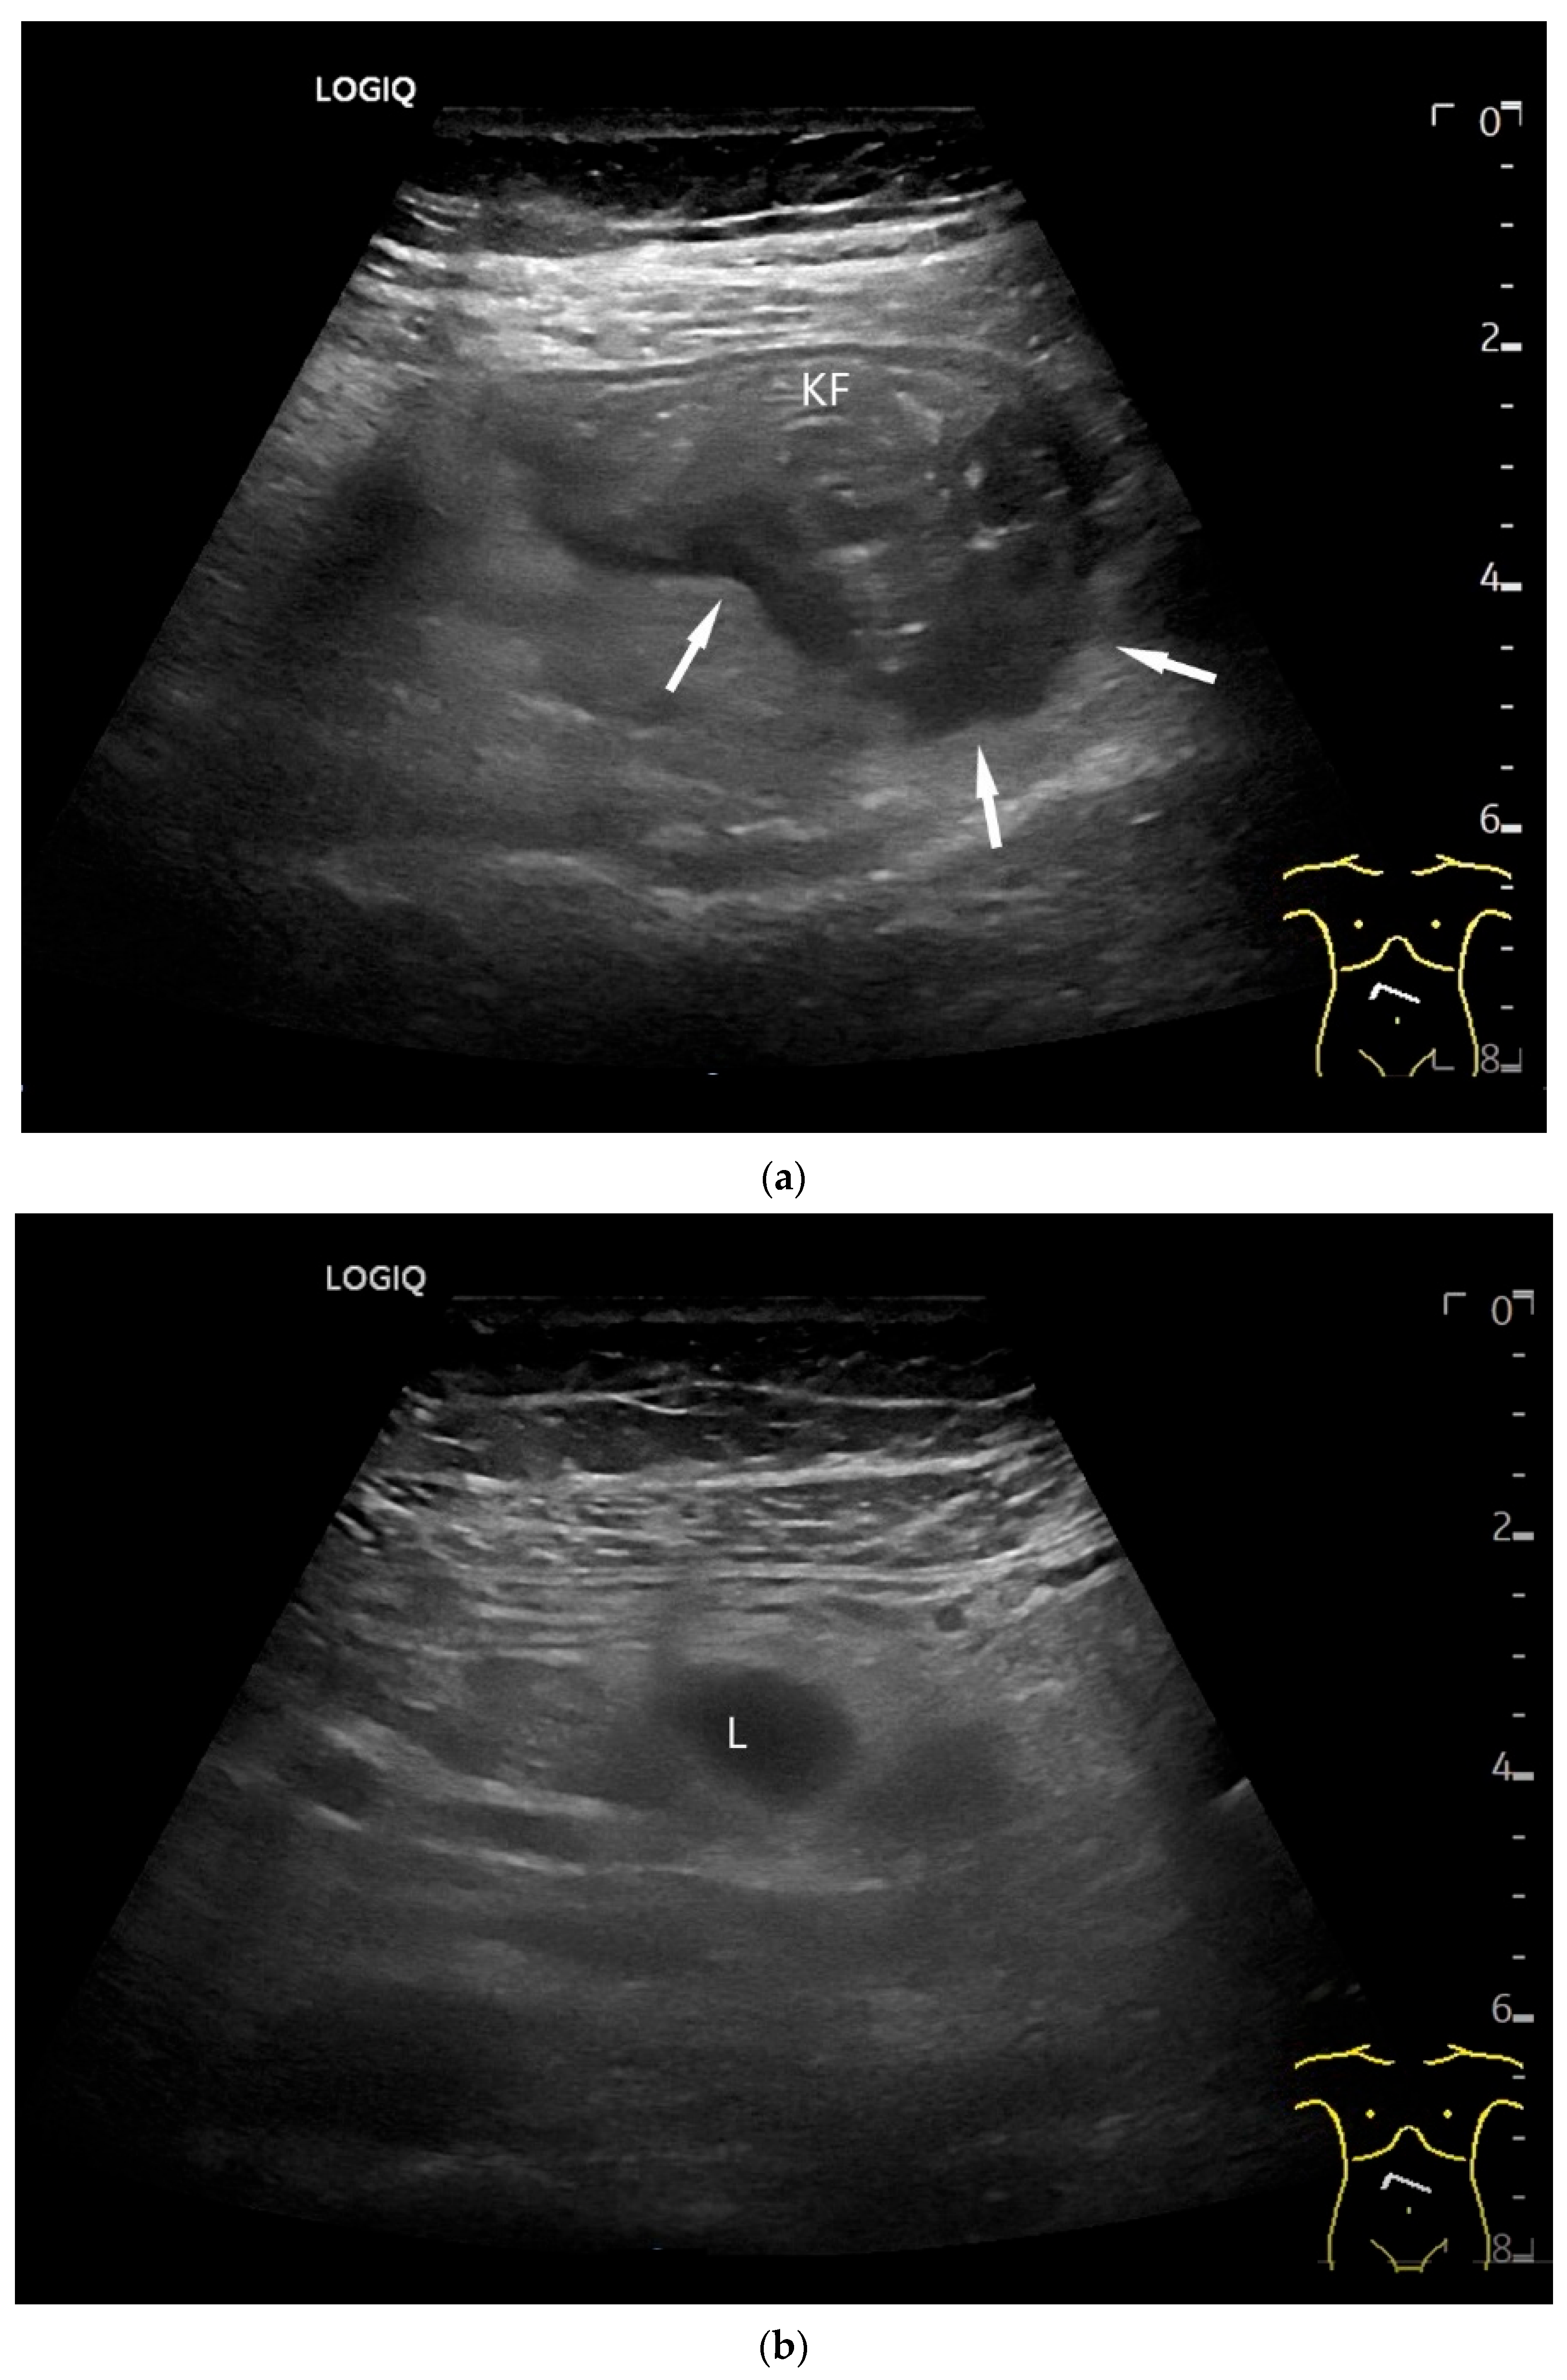

| Lymphoma | Very pronounced wall thickening with marked hypoechogenicity. Large regional and distant lymph nodes. Look for splenic infiltration. Tumor vessels on CDI and hyperenhancement on CEUS. Heterogeneous hyperechogenicity of the mesentery with walling of the mesenteric vessels. Multiple localizations are possible. |

- Cui, N.Y.; Gong, X.T.; Tian, Y.T.; Wang, Y.; Zhang, R.; Liu, M.J.; Han, J.; Wang, B.; Yang, D. Contrast-enhanced ultrasound imaging for intestinal lymphoma. World J. Gastroenterol. 2021, 27, 5438–5447. [Google Scholar] [CrossRef]